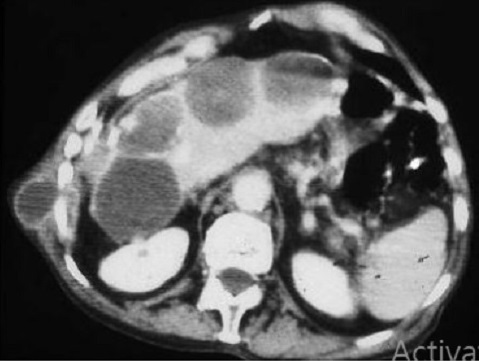

Aspect radiologique de

osteolyse de arch posterieue des côtes C5,6,7

droites ( flèche noire ) du osteite d'une SAPHO

syndrome . Plain film pulmonaire OAD |

Aspect radiologique TDM du osteite et

hyperostose articulation sternoclaviculaire droit en

coupe axiale d'une syndrome de SAPHO . Image

radiologique TDM en coupe axial |